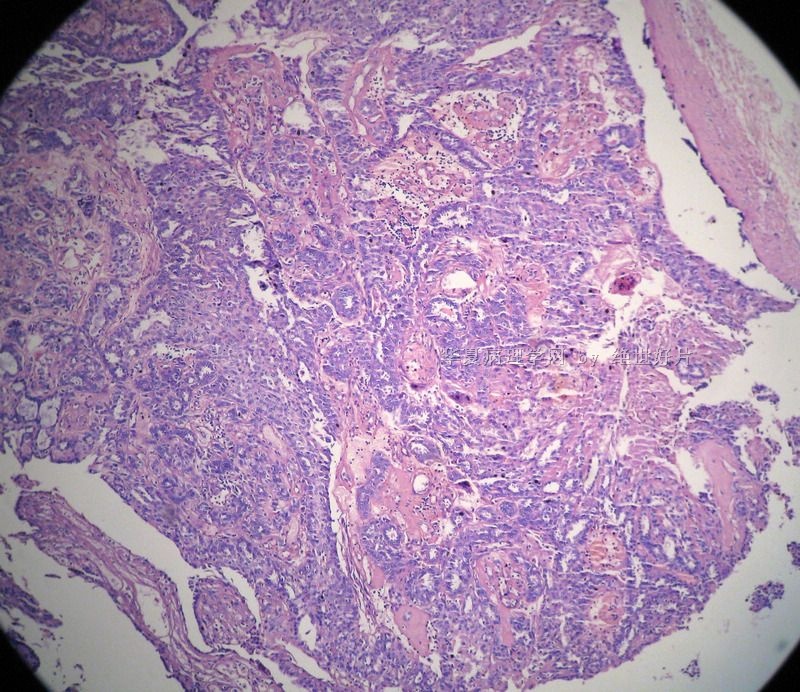

肝胆正常组织与肝癌胆管癌组织切片彩色图谱大全

图片尺寸3937x2250